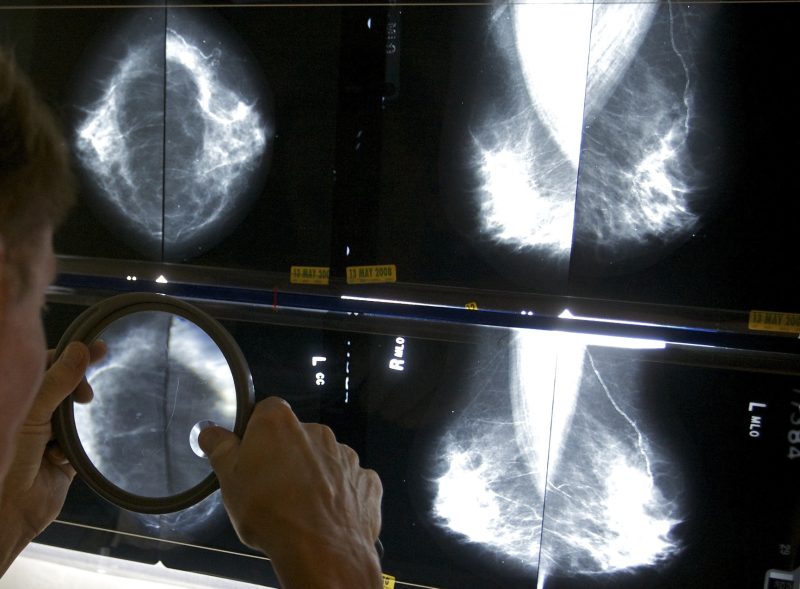

(NewsNation) — Mammogram providers are now federally required to tell their patients about their breast density, which not only increases the risk of cancer but makes it harder to detect.

“Dense breast tissue can make cancers more difficult to detect on a mammogram. Additionally, dense breasts have been identified as a risk factor for developing breast cancer,” the FDA said in a statement.

Having information about breast density could help patients handle their health better as “an important part of a comprehensive breast health strategy,” the FDA explained.

Those with dense breasts might require more than just a mammogram — like additional MRIs or ultrasounds — to assess cancer risks.